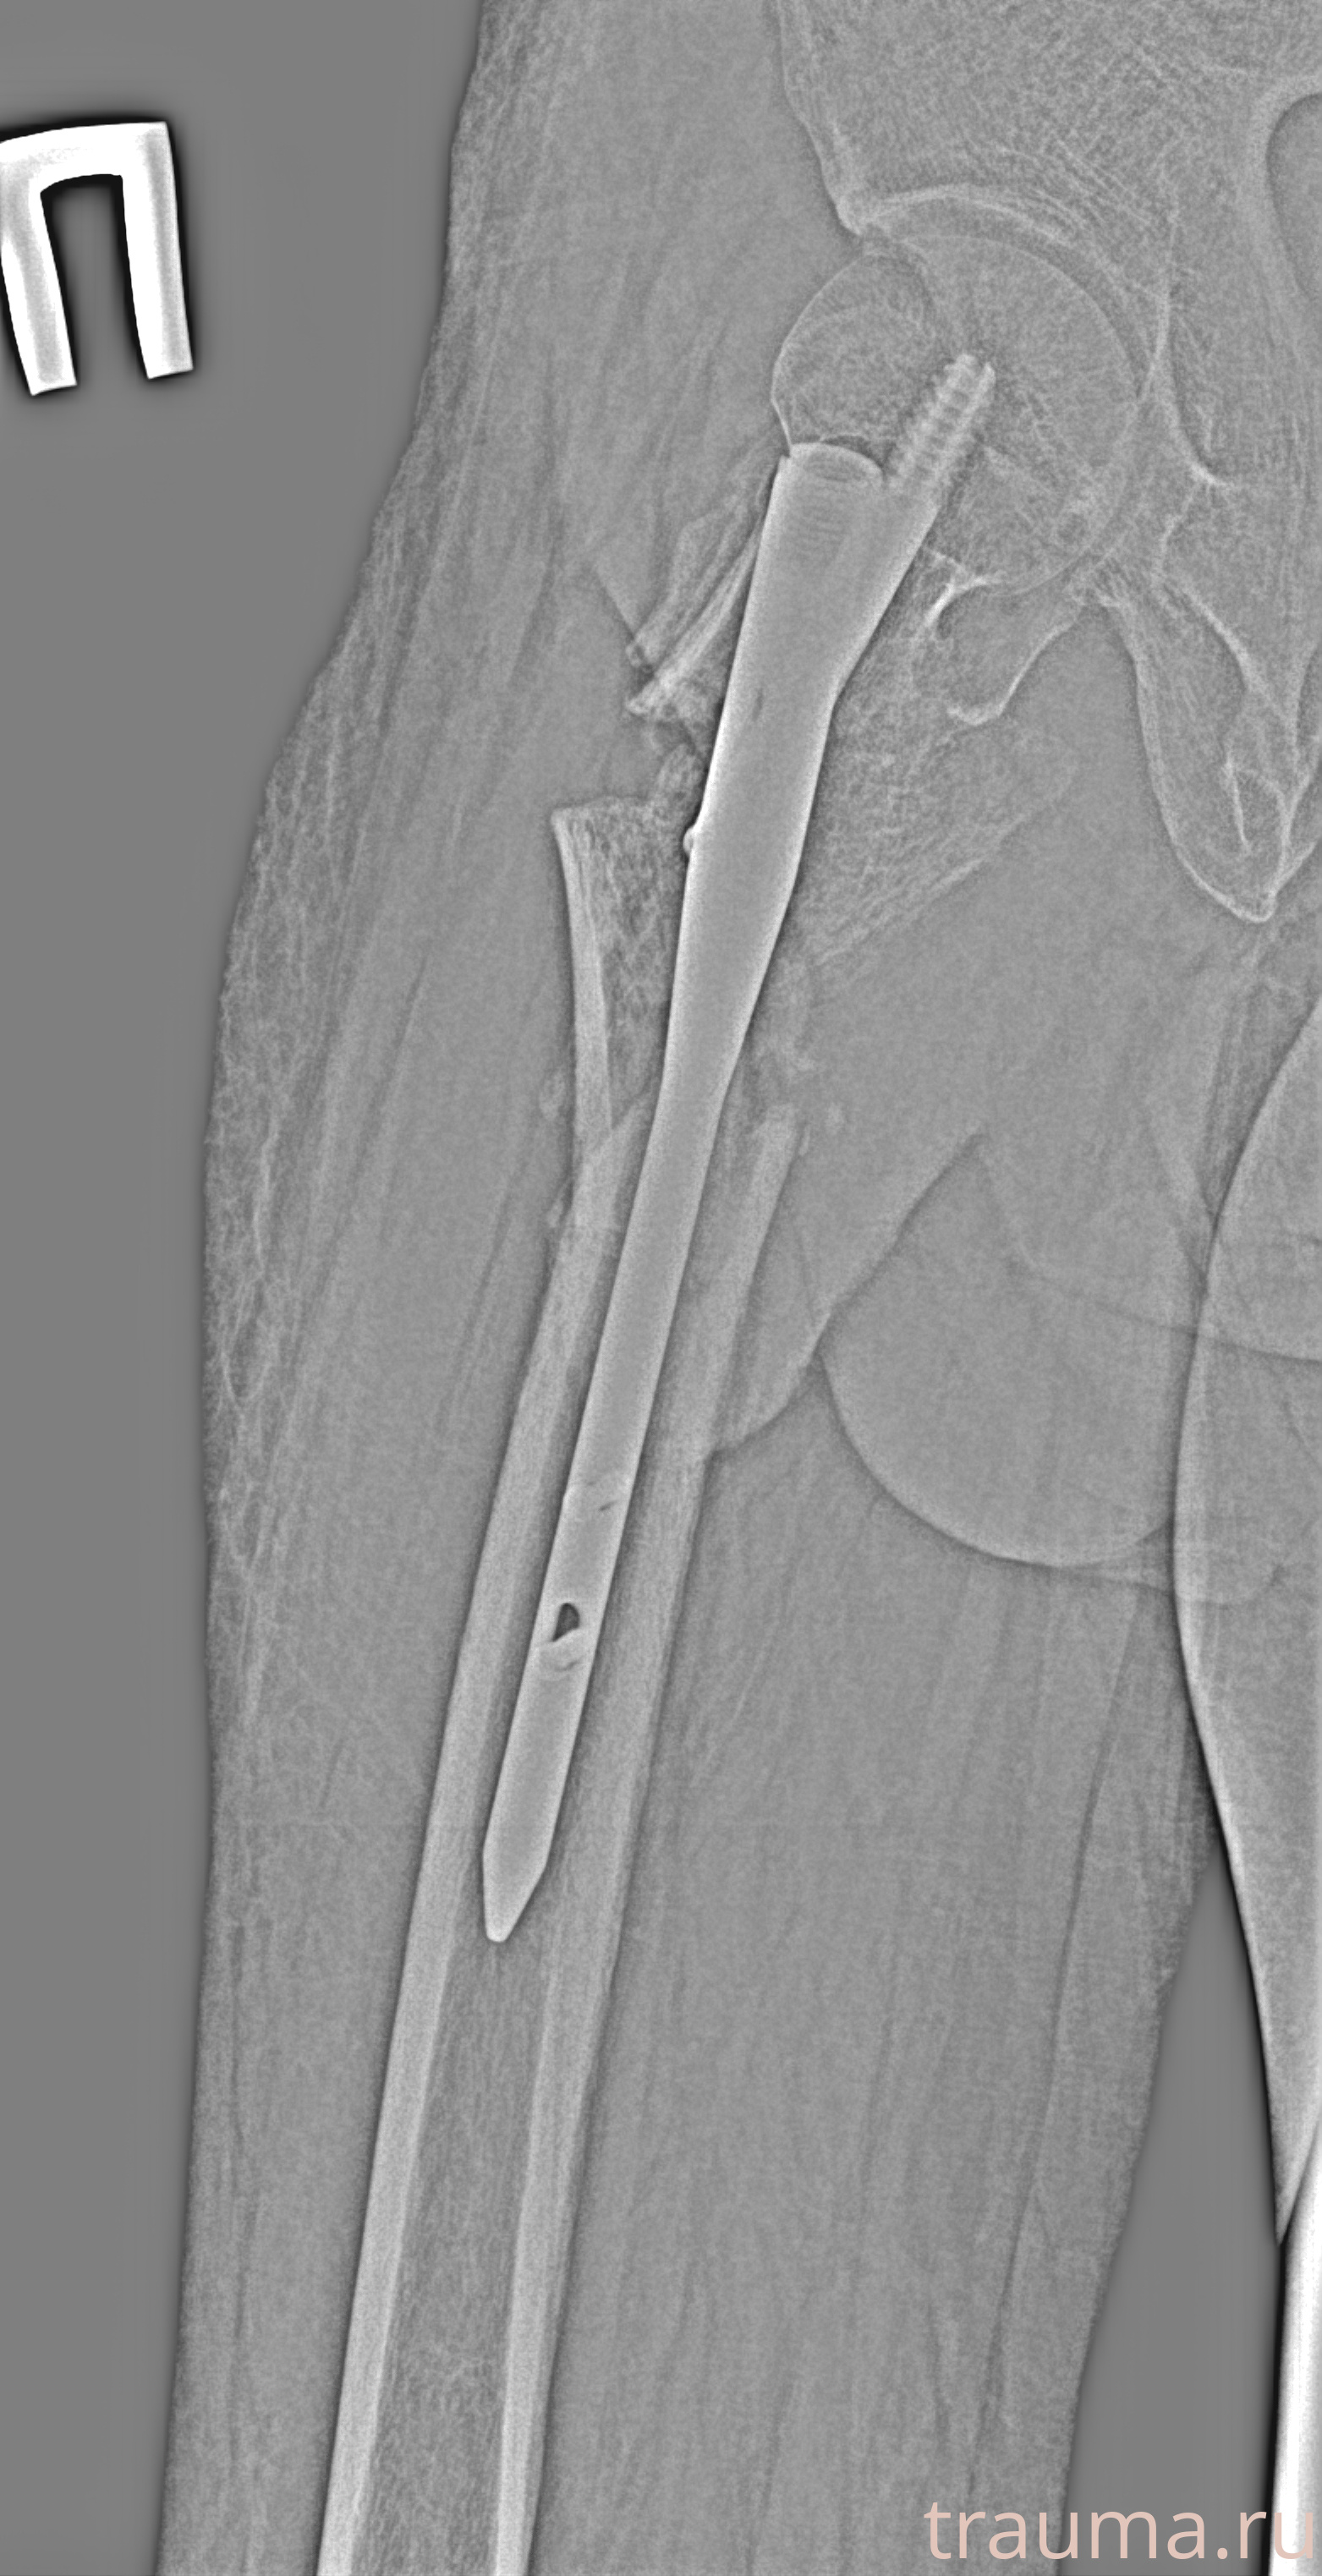

Рентген на дому: по вашему адресу приезжает врач-рентгенолог, травматолог-ортопед с мобильным рентгеновским аппаратом, проводит диагностику травмы или заболевания, делает необходимые рентгенограммы, дает рекомендации по дальнейшему лечению. Получить качественные снимки в домашних условиях возможно благодаря уникальной методике, разработанной МосРентген Центром для института  Склифосовского